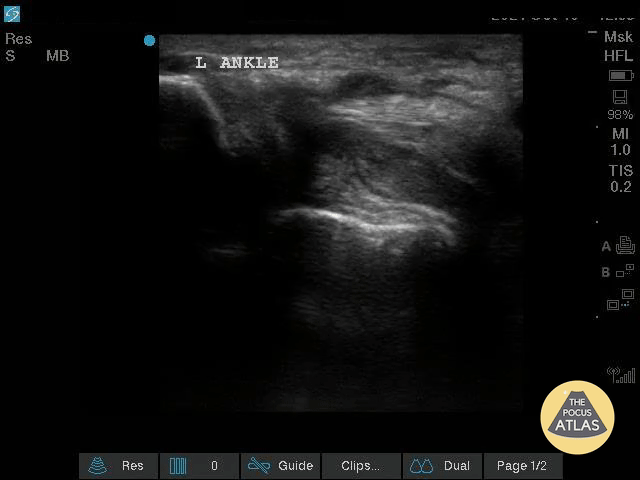

Musculoskeletal - Complex Left Ankle Effusion

This is an image of a left ankle demonstrating a complex effusion in a patient presenting with ankle pain and swelling. Arthrocentesis was performed confirming septic arthritis. Michael Macias